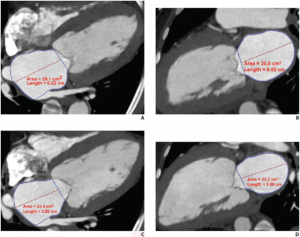

Cardiac CT angiography (CTA) derived left atrium emptying fraction (LAEF) improves predictive performance of established clinical risk scores and may be used to assess patients’ risk during pre-transcatheter aortic valve implantation (TAV) work-up and post-procedural surveillance.